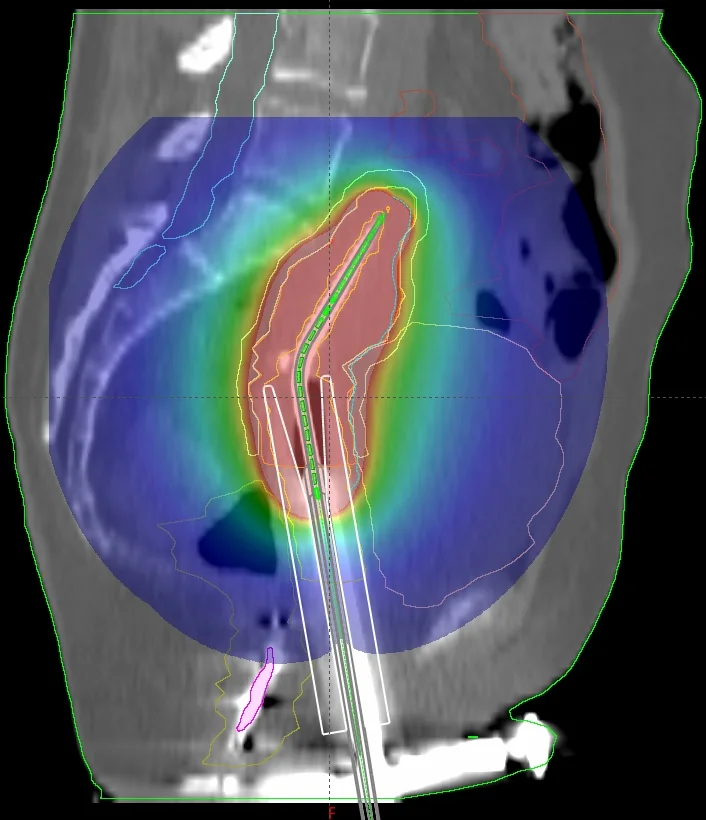

Der MammoSite-Applikator ist ein füllbarer sphärischer Silikonballon, der intraoperativ in der Kavität des entfernten Tumors platziert wird. Der wird Ballon wird mit einem Gemisch aus isotoner Kochsalzlösung 0,9 % und Kontrastmittel (z. B. in einem Verhältnis von 10:1) gefüllt. Das iodhaltige Kontrastmittel hebt den Ballon auf den CT-Bildern vom Brustgewebe ab, sodass er für die Bestrahlungsplanung gut konturiert werden kann. Eine zu hohe Kontrastmittelkonzentration (Empfehlung: <10 %) kann bei Berechnungen mithilfe des TG-43-Algorithmus, der zur Berechnung eine reine Wasserumgebung annimmt, zu großen Dosisabweichungen führen. Das liegt vor allem an dem hohen Iodgehalt in den Kontrastmittellösungen, das aufgrund seiner hohen Dichte zu Dosisreduzierungen führen kann, die vom TG-43-Algorithmus nicht berücksichtigt werden. In mehreren Sitzungen wird die Quelle durch einen Zweikanal-Katheter in den Ballon gefahren. Der Durchmesser des Ballons variiert je nach Patient und Ausführung des Ballons. Um den hohen Ansprüchen komplexer Dosisverteilungen gerecht zu werden, gibt es seit einiger Zeit Multilumen-Varianten (nicht sehr verbreitet in Deutschland), die unter Verwendung mehrerer Katheter weitere Haltepositionen ermöglichen.

Nach der chirurgischen Entfernung des Tumors, wird der MammoSite-Applikator eingesetzt und verweilt dort für die gesamte Behandlungszeit (ca. eine Woche). Am zweiten Tag wird ein Planungs-CT gefahren und basierend auf der Anweisung ein Bestrahlungsplan erstellt. In den letzten drei Tagen wird in je zwei Sitzungen pro Tag eine Dosis in einem bestimmten Abstand, in der Regel in 0,5 cm Gewebstiefe bzw. 0,5 cm von der Ballonoberfläche appliziert. Die Haut- und Rippendosis sollten eine Maximaldosis (z. B. 1,5 Gy pro Fraktion) nicht überschreiten, und bilden somit die limitierenden Faktoren der Behandlung. Je nach klinischer Erfahrung, variieren die Dosierungskonzepte und tolerierbaren Maximaldosen in den Risikoorganen.

Sofern in der Computertomographie um den Ballon große Lufteinschlüsse zu sehen sind (z. B. weil die Kavität das maximale Ballonvolumen überschreitet, oder dieser nicht vollständig aufgefüllt wurde) müssen diese ebenfalls berücksichtigt werden, da Dichteinhomogenitäten vom am weitesten verbreiteten TG-43-Algorithmus nicht berücksichtigt werden. Zu diesem bekannten Problem existiert bereits eine Reihe von Publikationen. Diese beschäftigen sich überwiegend mit den Auswirkungen vom Kontrastmittel, von Lufteinschlüssen am und im Ballon und mit dem Umgebungsmedium, dass im TG-43-Formalismus als Wasser angenommen wird, woraus eine erhöhte Rückstreuung resultiert.